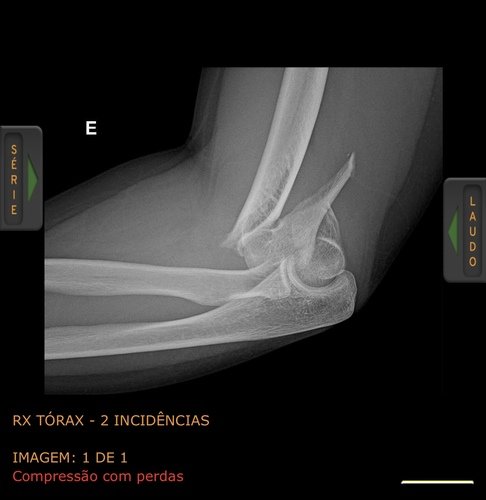

Olá sou Carine e fui vítima do acidente de trânsito ocorrido em 08/09/24 na ponte de integração Santo Tomé/São borja, quebrei em várias partes o cotovelo esquerdo onde precisei passar por uma cirurgia feita em 01/10, porém não obtivemos bons resultados somente com fios tendo a ter que passar por uma nova cirurgia particular para aplicar placas. Sou autônoma e estou sem pode trabalhar, sendo assim venho por meio desta vakinha pedir ajuda, toda ajuda é bem vinda. Desde já agradeço.